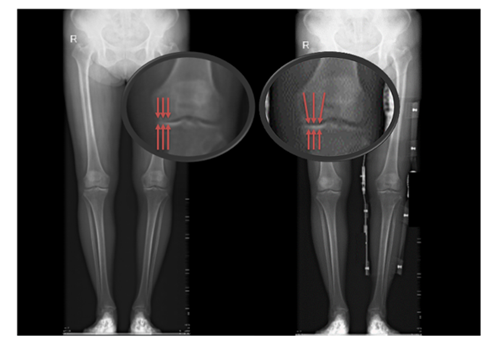

患者未佩戴(左)和佩戴(右)新型矫形支具负重位下肢全长X线片

患者佩戴矫形器行走,并通过步态实验对佩戴支具前后的步态数据进行测算、分析。实验数据结果初步证明,受试者佩戴膝关节内侧减压矫形器后,支撑相后期(膝关节承重的重要周期)膝关节外翻角增大,膝关节内侧力线向外侧转移,膝关节内侧压力降低。对于早、中期的膝骨关节炎患者,佩戴合理设计的膝关节矫形支具能够矫正下肢力线,从而减轻患髁受力,减轻疼痛、改善患处功能并增加膝关节稳定性。